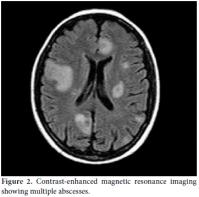

Drainage of the right temporal scalp nodular lesion yielded purulent material and showed Gram-positive bacilli. It later grew nocardial infection, but the specific species was unidentified because our hospital's laboratory could not make that determination. Daily doses of trimethoprim-sulfamethoxazole (TMP-SMX) 15 mg/kg were started. The azathioprine treatment was withdrawn, and the prednisolone dosage was decreased from 40 mg/day to 8 mg/day. In addition, the patient's blood cultures grew beaded, branching Gram-positive rods which were identified as nocardial infection, and high-dose ceftriaxone treatment (4 g/day) was added to the treatment regimen. Five days later, she suddenly developed dyspnea and a cough, and a chest X-ray showed prevalent miliary infiltration (Figure 1). Additionally, urgent thoracic computed tomography (CT) showed miliary nodular infiltration [miliary tuberculosis (TB)-type pattern that appeared to indicate an infection]. Therefore, a bronchoscopy was performed, but Gram staining of the broncoalveolar lavage (BAL) specimen showed no nuclear neutrophils, microorganisms, or acid-fast bacilli.